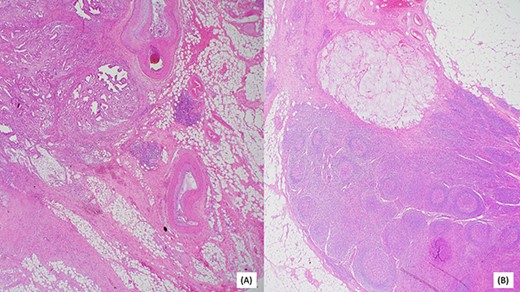

Invasive moderately differentiated adenocarcinoma with immunohistochemistry testing for mismatch repair proteins (MMR) significant for the loss of nuclear expression of PMS2 with retained strong expression of MSH2, MSH6 and MLH1.

Post resection, surgical pathology specimen revealed a 5.8 cm invasive moderately differentiated adenocarcinoma with mucinous features invading the mesenteric fat of the small bowel without lymphovascular or perineural invasion. Surgical margins were negative for carcinoma. Remarkably, 1 of 25 lymph nodes was associated with acellular mucin. Multiple deeper levels and immunohistochemical stain for CAM5.2 failed to reveal isolated tumor cells. Additionally, in the absence of any neoadjuvant therapy, the acellular mucin-associated lymph node was considered uninvolved by adenocarcinoma, as per AJCC conventions (Fig. 4) A histomorphological comparison of small bowel adenocarcinoma and prior cholangiocarcinoma was made at the intradepartmental consensus conference and the two tumors were deemed as separate primaries. The small bowel adenocarcinoma was staged as pT3N0. Genetic analysis of the tumor by sequencing confirmed the MLH1 gene [K618del] mutation, in addition, a common hereditary gene panel also revealed multiple mutations with lesser frequency. At the time of writing this report, the patient shows no radiological evidence of recurrence.

(A) Invasive moderately differentiated adenocarcinoma with mucinous features invading the mesenteric fat of the small bowel. (B) One of 25 lymph nodes associated with acellular mucin.